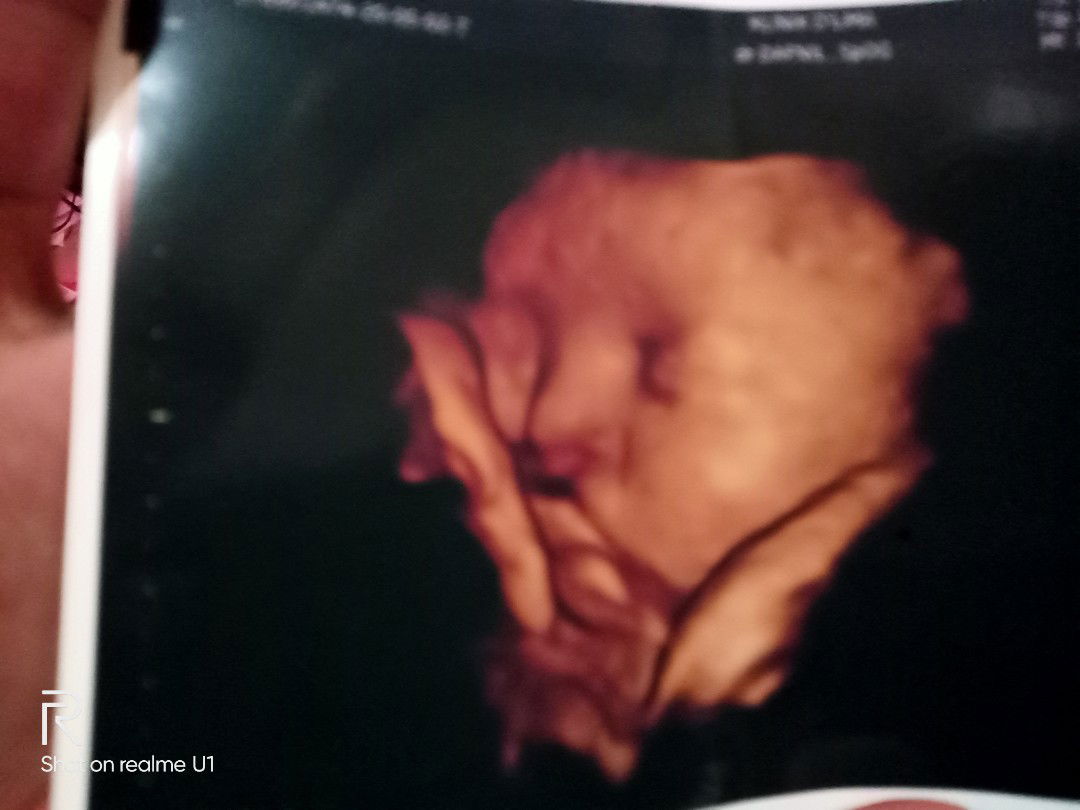

hasil foto usg

Bunda saya mau nnya sampe rumah saya kefikiran setelah liat cetakan foto hasil usg... Tdi usg dr nya blg smua Bagus dan normal kata dokternya bayi saya jg sudah masuk panggul... Agak payah jg td liat wajahnya... Coba liat foto anak saya di slide pertama kira kira bibir nya normal kah bun.... Atau evekk aja tu... ? Kefikiran.... Yg slide ke dua itu waktu saya usg usia 27w4d...